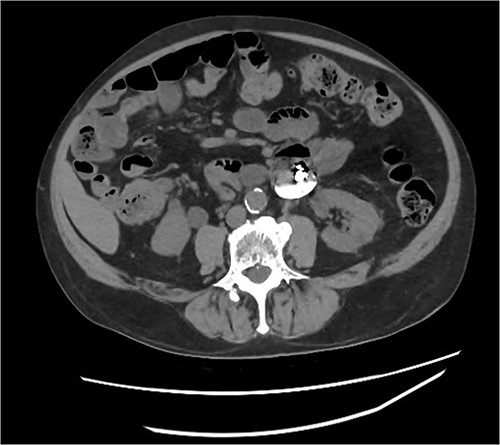

During the push enteroscopy the hearing aid could not be found despite thorough inspection of duodenal diverticula. The procedure was assisted by image intensifier guidance, and upon consultation with the onsite radiologist, the impression was that the hearing aid was in a jejunal diverticulum rather than a duodenal diverticulum. The procedure was abandoned and a single balloon assisted enteroscopy was planned for the following day. Prior to the procedure, the foreign body could not be located on the initial scout x-ray, and it was presumed to have passed naturally. Follow up formal x-rays again did not identify a foreign body (Figs 4 and 5), and the patient has been well since.